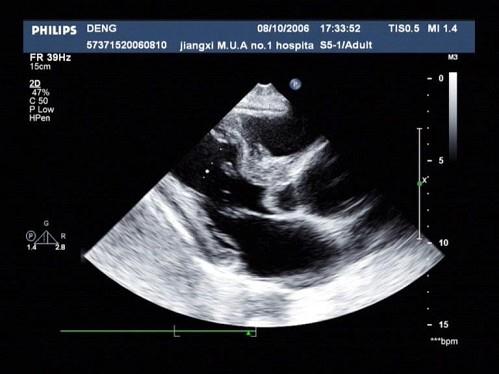

问题 患者,男,50岁,发热半月余,全身不适,乏力,食欲不振。根据超声心动图,最可能的诊断是?(?)

选项 A.风湿性心脏病 B.感染性心内膜炎 C.老年退行改变 D.主动脉瓣狭窄 E.冠心

答案 B